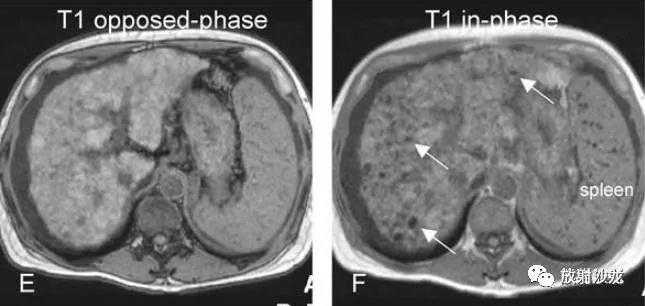

各基本序列信号特征

T2fatsat:未见病灶显示;

同反相位:反相位呈低信号,提示局灶性脂肪浸润;

ART:动脉期,由于脂肪抑制呈低信号,无明显强化;

DEL:延迟期,仍呈低信号。

DN-HCC转变,MRI表现:

A~D:影像表现如上所述。12个月后复查: